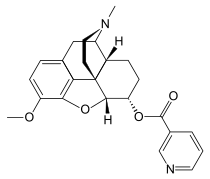

6-nicotinoyldihydromorphine 6-nicotinoyldihydromorphine |

Nicomorphine Nicomorphine | ||